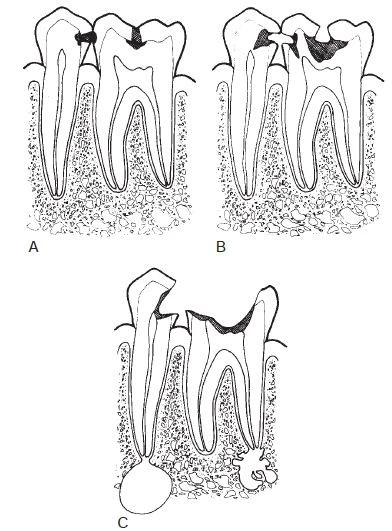

Hình 1. Quá trình mất khoáng ở mặt nhai và mặt bên đi từ men răng đến ngà răng và chạm vào tuỷ răng.

Hình ảnh thấu quang sớm của tổn thương trên men răng thông thường có hình tam giác với đáy rộng nằm trên bề mặt răng, mở rộng dọc theo trụ men, những hình ảnh phổ biến khác chẳng hạn như rãnh, một dấu chấm, một dải hoặc một đường mỏng. Khi quá trình mất khoáng hoá tiến triển đến đường nối men ngà, nó lan rộng dọc theo đường này, thường hình thành nên đáy của một tam giác thứ hai với đỉnh hướng về phía buồng tuỷ. Tam giác này thường có đáy rộng hơn ở men răng và tiến triển hướng về phía tuỷ răng dọc theo các ống ngà. Ngoài ra, cũng có thể thấy những hình dạng bất thường khác của quá trình mất khoáng.

Tổn thương sâu răng ở trẻ em và thanh thiếu niên hầu hết thường ở mặt nhai các răng sau. Quá trình mất khoáng hoá bắt nguồn từ men răng tại những hố rãnh – nơi mảng bám vi khuẩn tích tụ. Tổn thương lan rộng dọc theo trụ men và nếu như không có gì cản trở sẽ tiến vào đường nối men ngà, ở đây có thể thấy được một đường thấu quang mỏng giữa men răng và ngà răng.

Tổn thương măt nhai thường bắt đầu ở bờ thành của rãnh hơn là đáy rãnh và sau đó có khuynh hướng xuyên qua gần như vuông góc hướng về đường nối men – ngà. Những tổn thương sớm có hình ảnh trên lâm sàng như là phấn trắng, vàng, nâu hoặc đổi sang màu đen ở rãnh mặt nhai. Khi phát hiện những rãnh đổi màu với bề mặt nhai trên lâm sàng còn nguyên vẹn thì cần chụp X quang để xác định xem liệu một tổn thương sâu răng có vượt qua đường nối men ngà chưa. Nếu tổn thương không băng ngang qua đường nối men ngà thì có thể không thấy được trên X quang.

Hình ảnh X quang truyền thống của một tổn thương xuyên vào ngà răng là hình ảnh thấu quang với đáy rộng, thường nằm bên dưới một rãnh, trong khi đó ở men răng chỉ có những thay đổi nhỏ hoặc không thay đổi gì rõ rệt. Tổn thương mặt nhai càng sâu thì càng dễ phát hiện trên X quang.